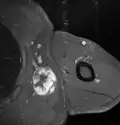

Histopathology of liposarcomas

Fig. 1 Micrograph of bone formation in a liposarcoma tumor -

Fig. 2 Micrograph of a dedifferentiated liposarcoma tumor -

Fig. 3 Lower-power micrograph of myxoid liposarcoma tumor -

Fig. 4 Higher-power micrograph of myxoid liposarcoma tumor

Fig. 7 MRI of myxoid liposarcoma of high grade, in the left axillary region of 40-year-old man, highlighted by its white color, in this horizontal section of the tumor.